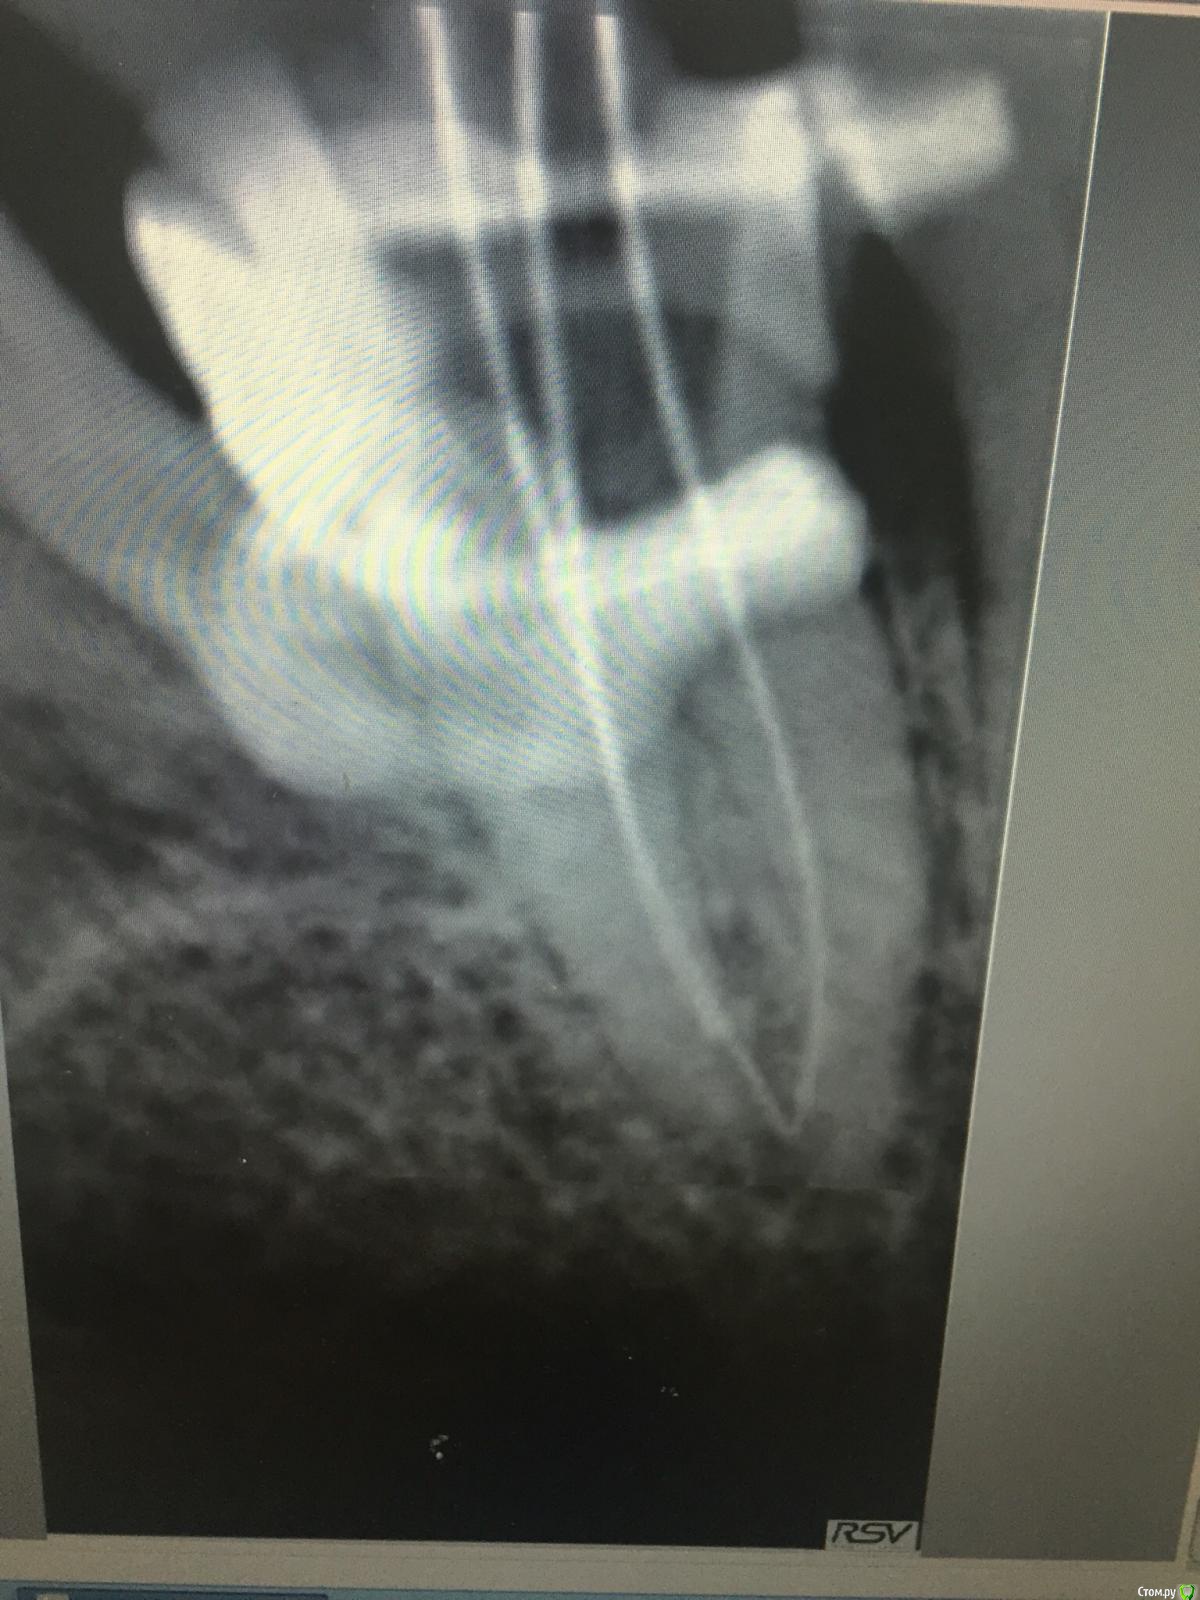

Ирина Игоревна Опубликовано 7 марта, 2018 Автор Поделиться Опубликовано 7 марта, 2018 вот что получилось . Показалось что неплотно как то, после немного подлатералила ещё . Пациент предупреждён о сложной анатомии. Договорились через 6 мес показаться на рг снимок для контроля. Ссылка на комментарий

ger_berra Опубликовано 7 марта, 2018 Поделиться Опубликовано 7 марта, 2018 В таких случаях много хлорки и уз.При обтурации латералкой-побольше силера после запечатывания апекса.Я полагаю,что эндо витальное? Ссылка на комментарий